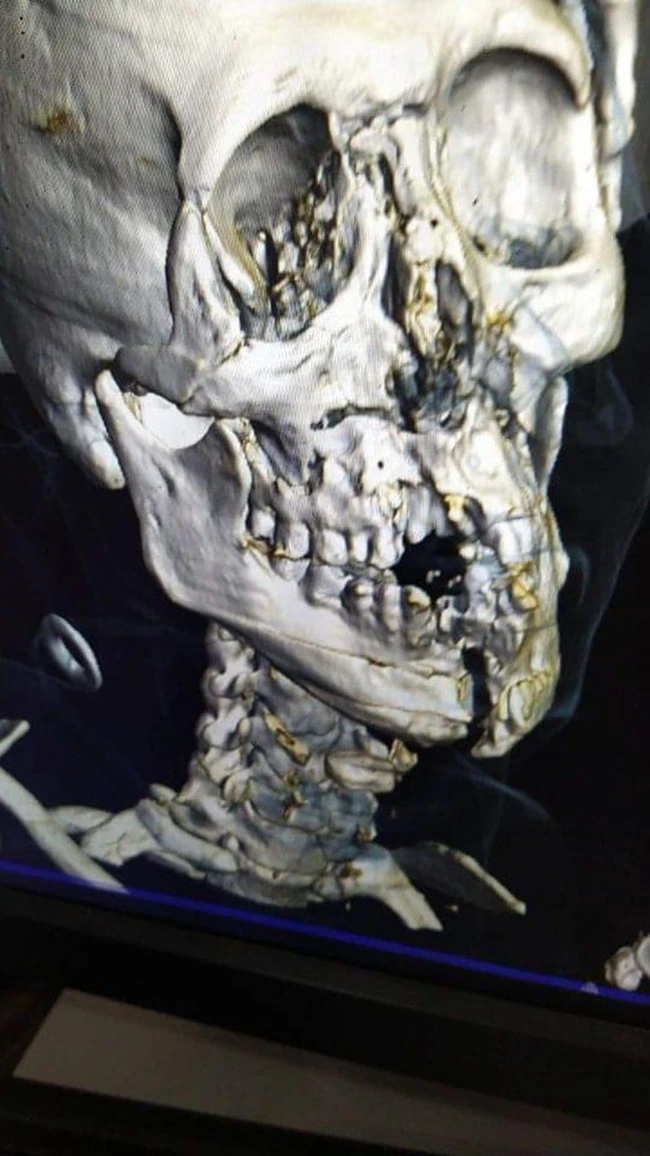

Așa arată radiografia craniului lui Al-Shahrani, care are pur și simplu bărbia despicată. Gulf News

Ziarele saudite au publicat și o poză cu radiografia craniului lui Yasser Al-Shahrani, care arată cu adevărat horror. Fundașul stânga saudit are maxilarul rupt și mai multe oase ale feței fracturate. El a suferit și hemoragie internă și va fi operat de medicii germani.